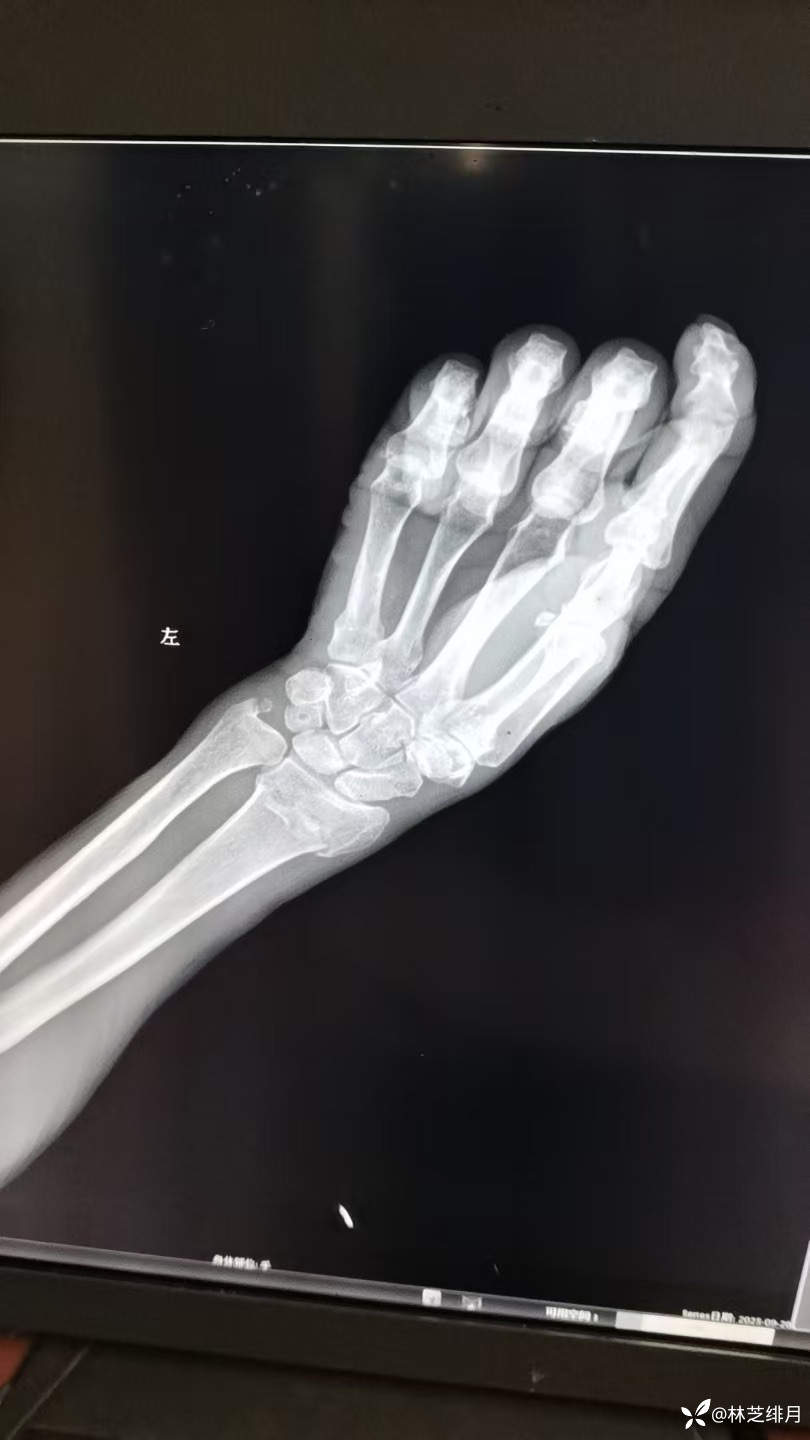

医院同时收了五个病人,有个88岁老爷子输完液准备回去,结果回去在我们医院摔了一跤,手直接肿胀畸形了。

当然得我出马,手法复位后纸板捆绑固定。

复位前的照片没有拍了。